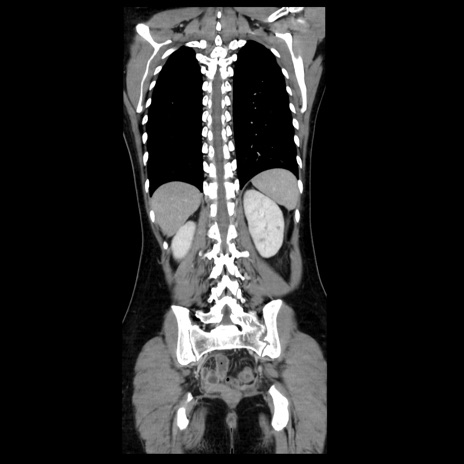

症例39(冠状断像)

【症例】40歳代女性

【主訴】上下腹部痛

【現病歴】2日目から下腹部痛あり。夜間は痛みで眠れなかった。昨日より上腹部痛と下痢が出現。臥位で痛みは軽快したため、休んでいた。本日になって臥位でも立位でも痛みが強くなってきたため救急要請。

【既往歴】子宮内膜症

【身体所見】部:平坦・軟、左上下腹部に圧痛あり、反跳痛あり。

【データ】WBC 21800、CRP 26.78

CT